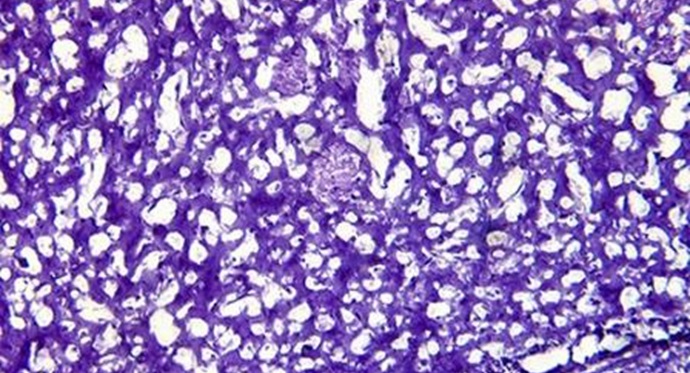

MI52倒置生物显微镜可对活体细胞,透明液态组织进行显微观察,也可以对培养皿中的培养组织进行动态显微观察。

MI52生物倒置显微镜MI观察小鼠细胞